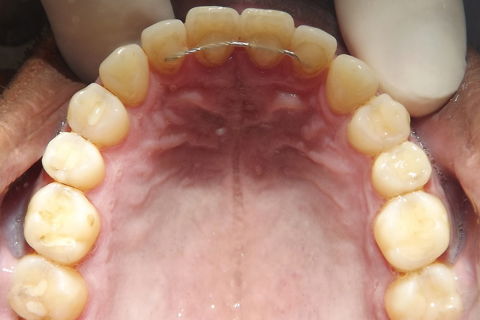

fotos iniciais do caso.

Paciente do sexo masculino, 36 anos, brauifacial. Relatava que os Diastemas lhe incomodavam muito, e em tratamento anterior o profissional fez exo de 2 incisivos centrais inferiores e instalou Prótese movel com 4 incisivos, após um tempo de uso a prótese começou a incomodar. em planejamento com o implantodontista ficou definido o fechamento dos diastemas e reabilitação dos elementos 41 e 31 com implantes.

segue as fotos do caso